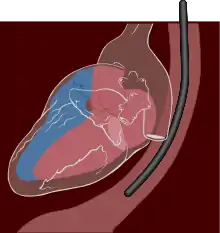

تخطيط عبر المريء

يتم تخطيط صدى القلب عبر المريء عن طريق مسبار يتم إدخاله عن طريق الفم إلى المريء، وذلك للحصول على "نافذة" أفضل موجات فوق صوتية|للموجات فوق الصوتية]] لرؤية الأقسام الخلفية من القلب، إذ أن هذه الجوانب تكون بعيدة عن الصدر، فتكون الصور التي يتم الحصول عليها من الصدر غير واضحة، بينما حينما يتم الفحص من المريء - الذي يُجاور القلب من الخلف مباشرة - أدق للأقسام الخلفية، كما يمكن إنتاج صور ثلاثية الأبعاد[5] لصمامات القلب.

يسمح التصوير عبر المريء بتحقيق تصوير بتمييز أعلى، وبخاصة للتفاصيل الدقيقة لحجرات القلب وصماماته، وذلك لأن المريء يقع مباشرة خلف القلب، بدون وجود الرئة كحاجز معيق بين مسبار الفحص وحجرات القلب، إذ أن الرئة بما تحتويه من هواء تعتبر معيقاً كبيراً لعمليات التصوير باستخدام الموجات فوق الصوتية. وتكون الدقة التصويرية أعلى من التصوير عبر الصدر[2] لأن المسبار يكاد يكون ملامساً للجدار الخلفي للقلب، ولايفصل بينهما إلا جدار المريء الدقيق نسبياً.

يمكن إجراء التصوير التصواتي عبر المريء بشكلٍ مشابه للتنظير الداخلي، حيث يُدخل المسبار - الذي يكون على شكل خرطوم (أنبوب) عبر البلعوم إلى المريء. يمكن أن يُصار إلى تهدئة المريض باستخدام منومات قصيرة الأمد، عندها يكون إدخال الأنبوب أصعب ولكن المريض لايلاحظ دخول الأنبوب فيشعر أن الفحص كان مريحاً أكثر. أو يمكن تشجيع المريض على التعاون وبخاصة إذا كان المريض يجري الفحص في عيادة خارجية ويرغب مثلاً في قيادة السيارة أو القيام بعمل ما بعد الفحص. يُشترط لإجراء الفحص أن تكون المعدة فارغة، ولذلك لابد أن يمتنع المريض عن تناول الأطعمة ل 6 ساعات على الأقل قبل الفحص، وعن شرب السوائل لمدة ساعة إلى ساعتين قبل الفحص وذلك لتجنب التقيؤ أثناء الفحص.